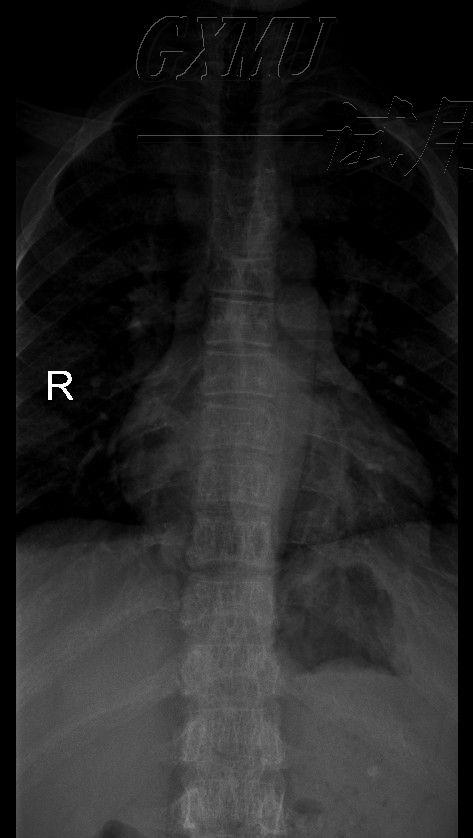

胸椎X光

胸椎X光,颈椎x光